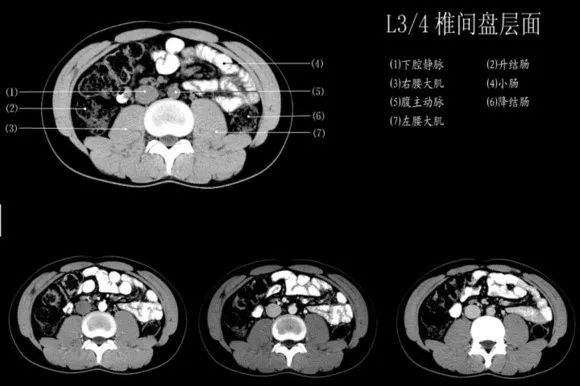

腹部ct太复杂 专家分享干货 手把手教你变身腹部ct高手 胆囊 胰腺 腔静脉 主动脉 肠系膜 网易订阅